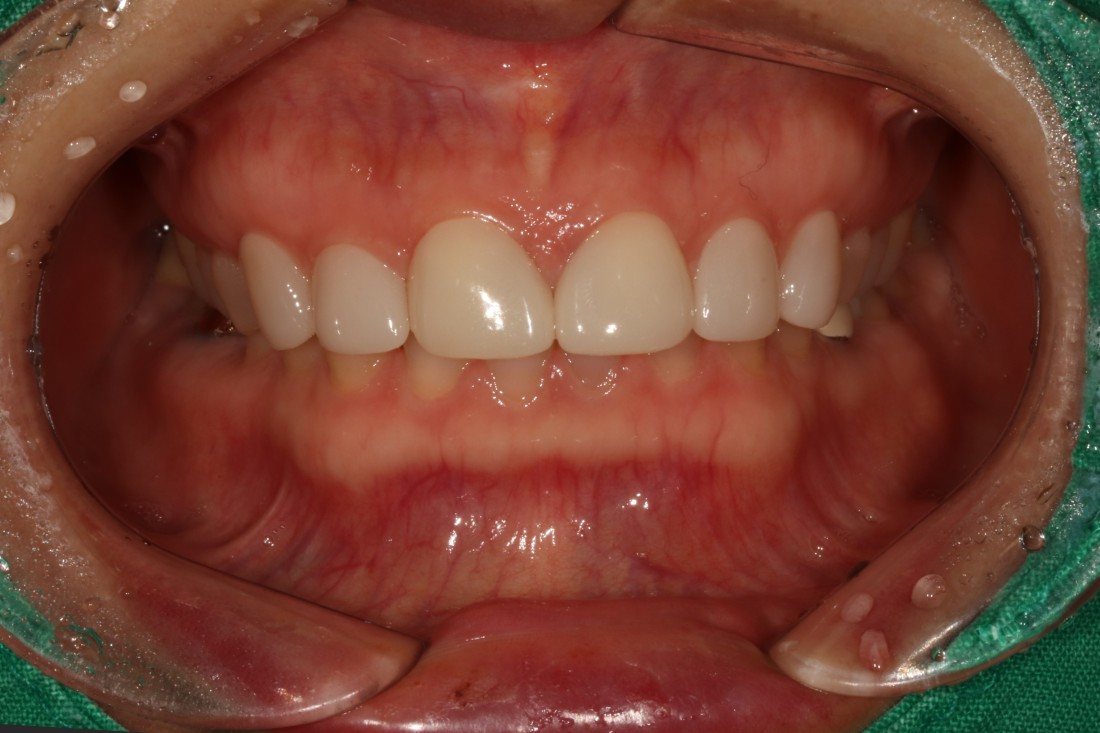

대표원장이 직접 전/후 사진을

비교하며 포스팅 해오고 있는

광주 무삭제 라미네이트

실제 사례는 위의 링크를

클릭하시면 보실 수 있습니다.

압도적인 실제 사례 케이스 건수로

증명하는 광주 무삭제 라미네이트 치과의

실력입니다.